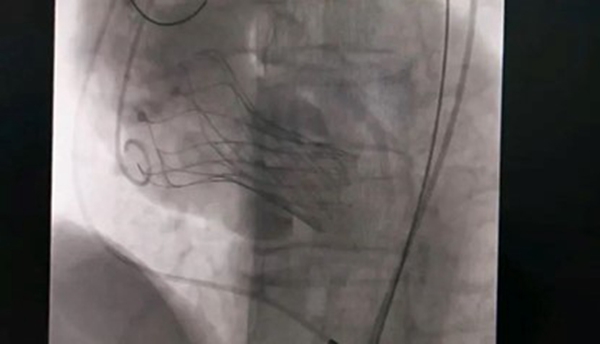

人工瓣膜置入中。重慶西區醫院供圖

10月18日,該患者實施手術,在新橋醫院專家的指導下,心血管內科主任宋明寶帶領團隊把瓣膜置入心臟。

宋明寶介紹,正常情況下,主動脈瓣完全打開后,瓣口面積在3-4平方厘米,如果瓣口面積在1平方厘米以下,則為重度狹窄,而該患者的瓣口面積僅0.51平方厘米。主動脈瓣不能完全打開,好比“心臟閥門”活動不暢,血液不能順暢進入主動脈。為適應這一變化,患者左心室不斷增大收縮壓力,導致左心室不斷擴大,心臟功能衰竭,隨時有猝死可能。術后,患者狀態良好,達到治療預期。(重慶西區醫院)